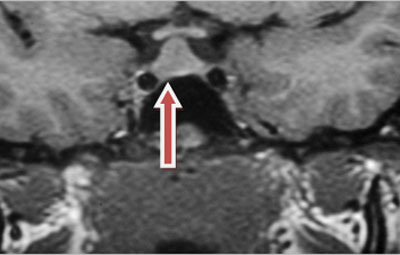

Ressonância nuclear magnética (RNM) mostrando macroprolactinoma

Do acervo do Dr. Faidon Harsoulis, MD; usado com permissão